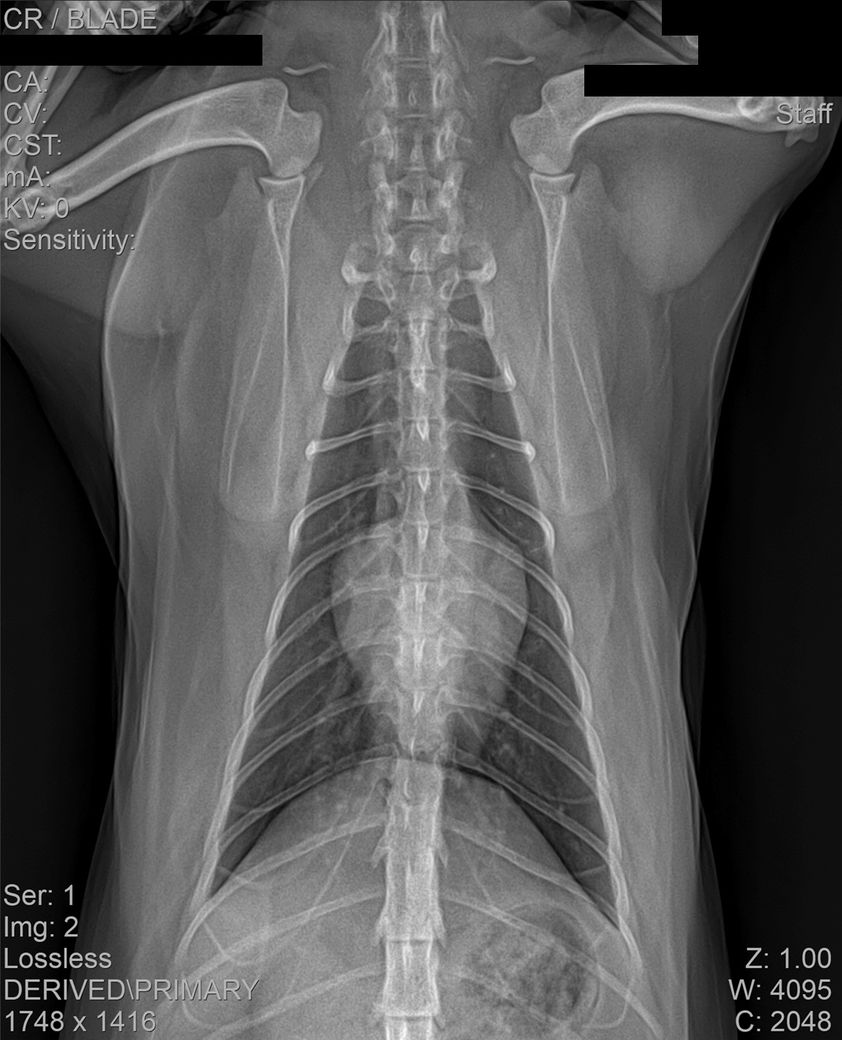

건강검진 때 받은 사진입니다

건강검진 받은 병원에서는 따로 소견을 주지 않으셨으나 지인이 이 사진을 보고

자신의 첫째 고양이가 진단 받았었던 HCM과 엑스레이 사진이 유사하다는 말을 들어서요

HCM의 경우 방사선 상으로는 완전히 진단하는 것이 어렵습니다.

HCM이 심할 경우 심장 모양이 valentine shape으로 보이기도 합니다. 아무래도 수의사 선생님이 이런 양상으로 HCM 가능성을 말씀하신 듯하니 심장초음파 진료가 가능한 병원 가셔서 검사 해보시기 바랍니다.

HCM의 진단의 golden standard 는 심장초음파 검사입니다. 하지만 첨부된 자료에는 심장 초음파 검사 결과가 없고

흉부 방사선 검사 또한 외측상이 결여되어 있어 자료로 판단할 수 없습니다.